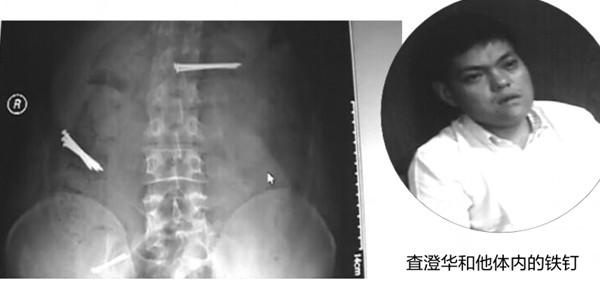

近年来,一位名叫査澄华的男子屡屡出现在全国不少地区,他经常会吞下数枚铁钉,然后向医院或警方求救,但又谎话连篇,编造自己的身世,因此被人在网上冠以“吞钉男”的外号。日前,他出现在蚌埠市,吞下9枚钉子,并要求医院给其注射杜冷丁,遭拒后又悄然离去。

鉴于这名男子有诸多可疑的行为,民警在网上进行了查询,原来,这名“吞钉男”早已被多家媒体报道过,该男子真名叫查澄华,家住江阴华士镇,他因为性格怪异多次离家出走,在流浪期间,他数次用同样的谎言和手法,博得社会关注。

经查询,仅在2012年6月份,査澄华就曾出现在三个地方的医院,每次都是因吞下钉子来求救,足迹遍及江浙一带,这些地方的媒体都对其进行过报道。 6月12日,他曾出现在浙江省中医院,声称被一个犯罪团伙控制,被迫吞下钉子;6月下旬,他以被强迫吞钉为由,先后向无锡市区和江阴市的两家医院求救;7月4日,他出现在南通市,自称姓李,是杭州人,被人骗到盐城从事传销活动,因拒绝加入被强迫吞下铁钉;7月9日,他来到常州,声称被养父母强迫吞下铁钉。

因查澄华腹中尚有钉子没有取出,警方表示,市民如发现查澄华求助,可及时与警方联系。-安徽商报